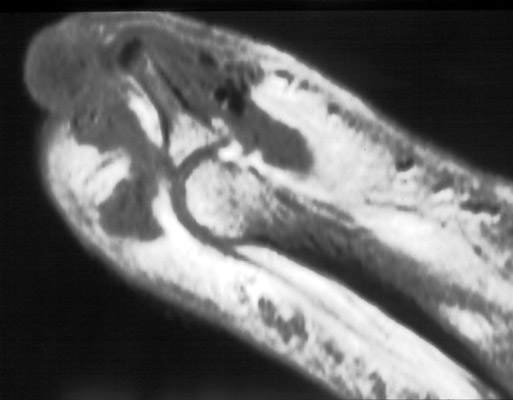

Gout

images/LARGE/72goutMRcor.JPG

images/LARGE/71goutMRsag.JPG

images/LARGE/73goutMRaxt2.JPG

images/LARGE/74goutMRaxpd.JPG